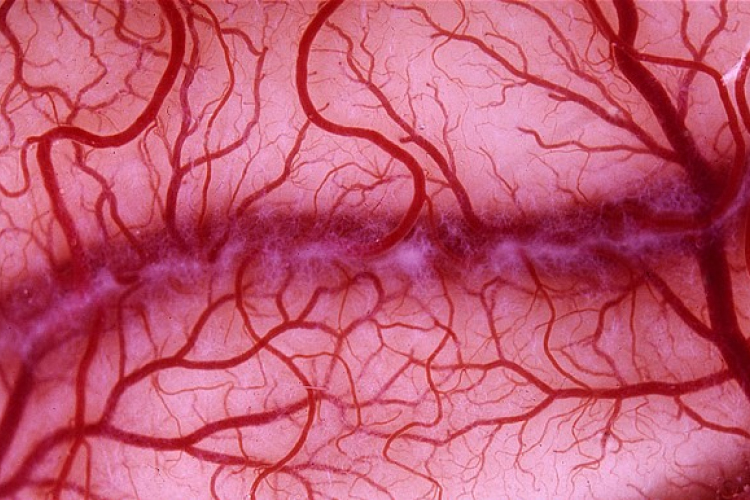

Őssejtből állítottak elő mesterséges vérereket amerikai orvosok

Őssejtekből állítottak elő amerikai orvosok mesterséges vérereket, amelyek azután akár kilenc hónapon át működőképesek maradtak.